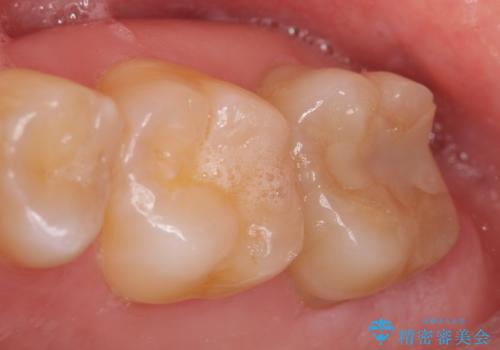

![[根管治療・セラミック補綴] 歯ぐきを押すと痛いの症例 治療前](https://seimitsushinbi.jp/wp/wp-content/uploads/2020/06/af6939fea203eb3874487b1710bde0f0-500x350.jpg?v=1591340021)

オールセラミッククラウン 奥歯のブリッジ